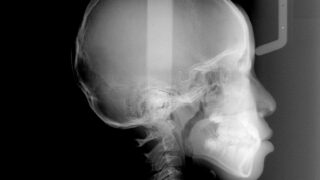

8歳、前歯部クロスバイトの1期治療

インビザラインfirstは、歯列の拡大と、個々の歯の整列を同時に行うことができます。従来の方法だと、拡大床の後に、ユーティリティーアーチを使用していたのですが、簡単に早く治療を行えます。 初診時年齢8歳主訴前歯の反対咬合診断前歯部クロスバイ...

下顎前突と横顔の改善

インビザラインfirstで、反対咬合を改善したケースです。前歯部のクロスバイトの改善と共に、下顎の位置が正しい位置になりました。歯並びの改善と共に横顔が綺麗になっているのがわかります。